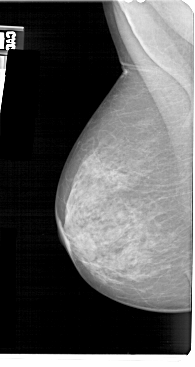

A_1465_1.LEFT_MLO

LEFT_MLO LINES 5491 PIXELS_PER_LINE 2911 BITS_PER_PIXEL 12 RESOLUTION 43.5 NON_OVERLAY